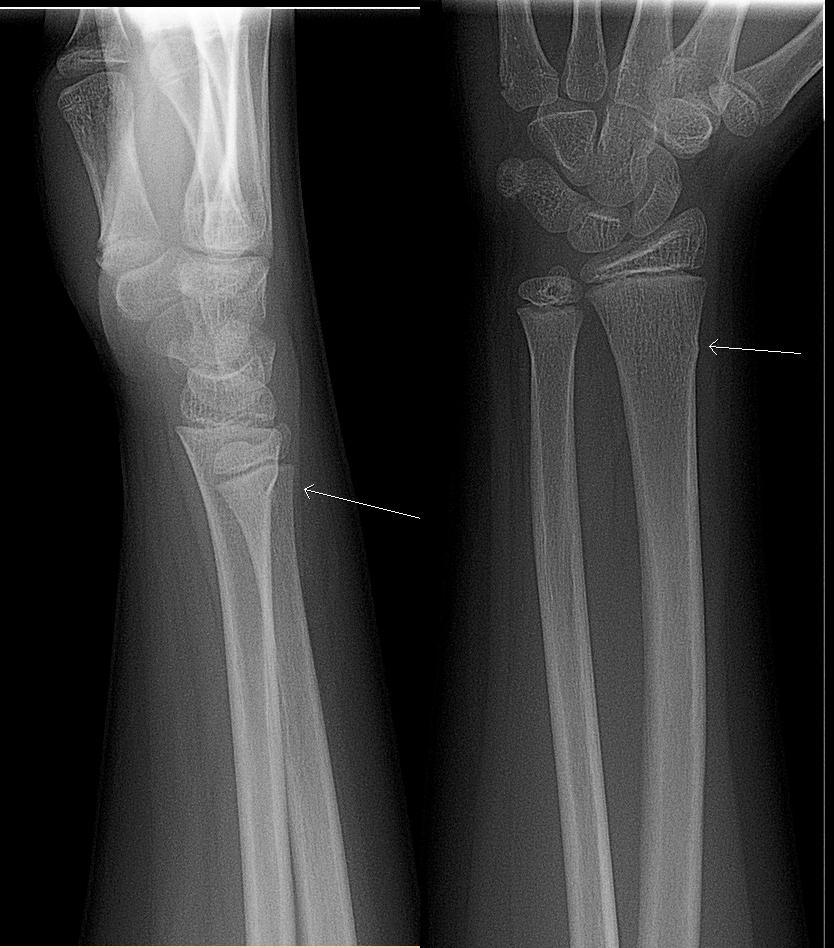

Often a child's forearm bone doesn't break fully but just gets distorted at the surface. This is called a 'greenstick' fracture and doesn't need an operation: it heals in a plaster cast. This X-ray shows a greenstick fracture at the white arrow: just a small bulge of the edge of the bone, rather than a break all the way across:

Greenstick fracture

By Lucien Monfils (Own work), CC BY-SA 3.0, via Wikimedia Commons